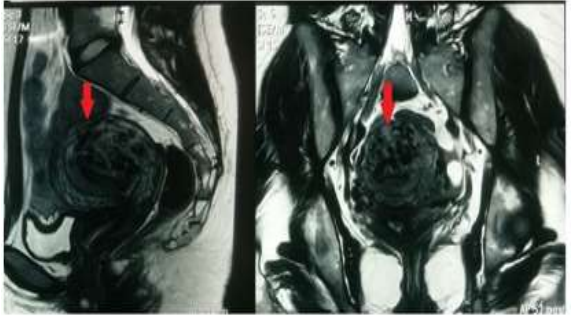

Shintre and Coelho [16] reported a 27-year-old lady who was known to have Thalassemia minor who had manifested with heavy vaginal bleeding and passage of clots over the preceding two days. She stated that she had been having continuous on and off mild to moderate vaginal bleeding pursuant to a second trimester therapeutic abortion she had undergone two months preceding her presentation. She did undergo therapeutic abortion in view of the fact that she had her chorionic venous samples which had shown that the foetus had Thalassemia major due to the fact that both herself and her husband had Thalassemia minor. The therapeutic abortion was induced with utilization of misoprostol (PGE1) tablets. The reports of the obstetrician who undertook the therapeutic abortion did document that the abortion was complete and therefore no curettage was undertaken pursuant to her abortion. She had also undergone another therapeutic abortion 8 months earlier for the same reason following chorionic villous sampling that showed Thalassemia major foetus. This therapeutic abortion was ensued by curettage of her uterine cavity for complete evacuation of her products of conception. She did not have any significant past medical or surgical history. She was noted to be pale or otherwise her general examination was normal. She had speculum examination of her vagina which showed a partially open cervical os that associated with minimal blood clots. There was no active bleeding. Her uterus was bulky, and it measured about 8 weeks to 10 weeks size as well as it was firm to soft in consistency, firm to soft with regard to consistency, mobile and associated with free fornices. The results of some of his laboratory blood tests included: Haemoglobin 9.5 grams per decilitre, platelets 3-lakhs, Serum Beta Human Chorionic Gonadotrophin (B-HCG) 35 MIU/ML which was normal, normal coagulation screen and normal liver function tests. Her blood sample was sent for grouping and saving for future use when required. She had ultrasound scan and magnetic resonance imaging (MRI) of pelvis. The MRI scan demonstrated a bulky uterus that measured 4 cm x 7 cm x 7 cm, heterogeneous lesion within the posterior wall of her uterus, lost endometrial-myometrial interface, multiple dilated tortuous blood vessels within her posterior myometrium which had suggested the likelihood of retained products of conception or gestational trophoblastic tumour which would represent placental site trophoblastic tumour, or uterine vascular malformation (see figure 1). The trans-abdominal ultrasound scan of pelvis did demonstrate an 8.8 cm x 7.5 cm x 7.5 cm bulky uterus the posterior myometrium that was very enlarged as well as heterogeneous with increased vascularity upon Doppler ultrasound scanning (see figure 2). Doppler ultrasound scanning did demonstrate a peak systolic velocity (PSV) of 121 cm / s as well as restrictive index of 0.36. The ultrasound scan also demonstrated that her endometrium was thickened within the lower uterine segment that was suggestive of retained products of conception. She had a chest x-ray which was normal. She had ultrasound scan-guided evacuation of her retained products of conception from her lower uterine segment which was sent for pathology examination. The evacuation of the products of conception did trigger active bleeding. She therefore underwent uterine artery embolization with utilization of cyanoacrylate (glue) (see figure 3). There was no evidence of active bleeding pursuant to her embolization. She was discharged on the 3rd post-procedure op day on oral antibiotics and haematinics. Pathology examination of the tissue did show degenerated and necrosed bits of decidua as well as few degenerate chorionic villi that were admixed with fibrin and blood. The degenerate products of conception did not show pathology examination features of placental site tumour trophoblastic. At her 6-weeks follow-up assessment she stated that her vaginal bleeding had diminished gradually over a period of 4 weeks and the bleeding stopped completely after 4 weeks. She had ultrasound scan of her pelvis with Doppler scan which did show diminished size of the arteriovenous fistula and with diminished vascularity (see figure 4). Shintre et al. [16] stated that the first case of AVM of the uterus was reported in 1926. [17]

MRI pelvis-sagittal and transverse section-showing bulky uterus with 4 x 7 x 7 cm sized heterogeneous lesion seen in posterior wall, lost endometrial-myometrial interface, multiple dilated tortuous blood vessels in posterior myometrium & tiny enhancing area within the endometrium in lower uterine segment. Reproduced from: [16] Shintre H S, Coelho K S. Managing Uterine Arteriovenous Malformation (AVM) Is Like Dealing with Raging Wildfire Awaiting A Spark: Better Be Extremely Cautious & Be Ready with Counter Measures Like Uterine Artery Embolization (UAE). Obstet. Gynecol. Int. J. 2017; 6(1): 00195 DOI: 10.15406/ogij:2017.06.00195